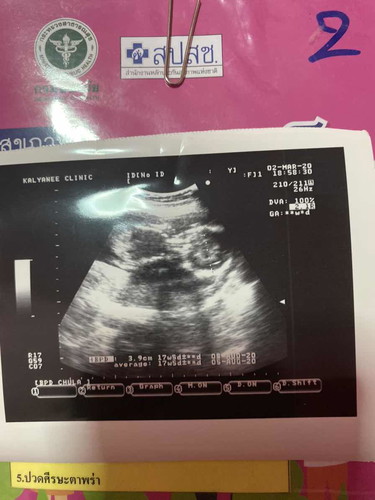

แม่บ้านไหนเป็นบ้าง 17w6 รวมวันนี้ มะวานไปหาหมอซาวเพศ คือท่านอนลูกเรา เอามือทั้ง2ข้างจับท้ายทอย นอนเหยียดขายาว ตอนหมอบอกดูภาพตอนนั้นยังขำ? แต่ดูช่วงเพศมองไม่เห็น หมอเลยบอกว่าน่าจะ เพศ ญ 80% แต่หมอบอกอย่าพึ่งเชื่อนะ ขอซาวใหม่สิ้นเดือนนี้ แม่บ้านไหนซาวแล้วเป็นแบบเราบ้าง แต่สำหรับเราได้หมด ช ญ ?